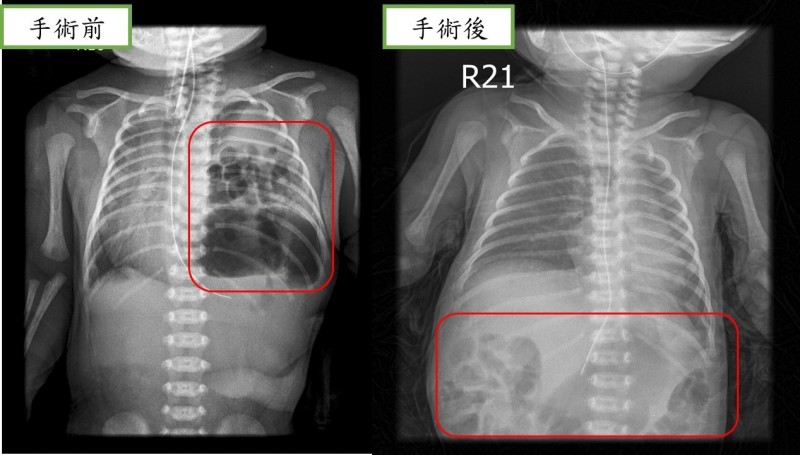

近日,重醫附屬兒童醫院心胸外科醫護團隊為這名男孩進行了手術,幫他將腸道送回腹腔,再補好了腹腔和胸腔中間膈肌的殘缺。手術順利完成。醫師提醒,孕產婦孕期一定按時要做好產檢,先天性膈疝最早可以在孕12周左右做產檢時通過彩超發現,如果孕期診斷,還應與其他畸形進行鑒別,同時根據多個指標評估胎兒膈疝病情的輕重,決定進一步處置方案。